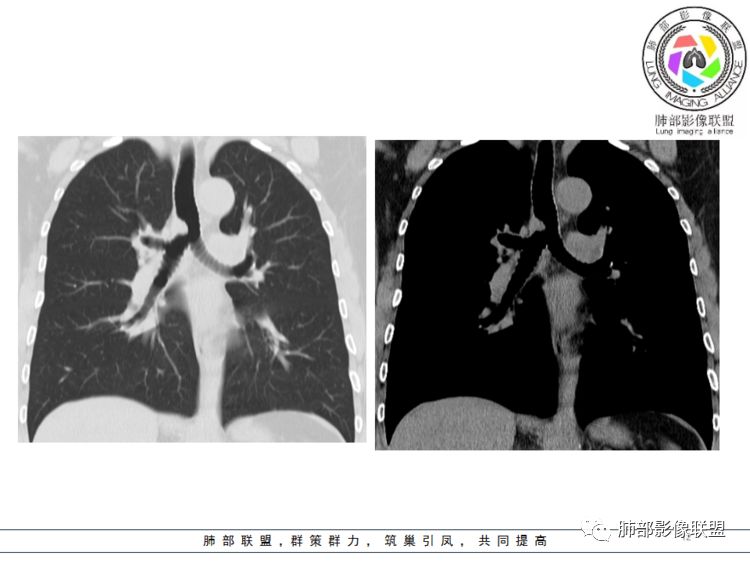

病灶跨气管壁内外,主体在外;边界清,密度均匀

明显看到气管壁软骨受压内移

局部是撑开的,就是说软骨不是破坏

南边分析:针对本例,病灶跨气管壁内外生长,常规跨内外的有:恶性肿瘤为主,其次就是神经源性、平滑肌瘤;常规的思维:跨内外就要看结构的变化气管的优势在于软骨相对密度高,而且成C型

我们如何分析这个病例?冠状位:软骨密度稍高;病灶区软骨部分区域不连续,外围连续,提示病灶推移为主,不是破坏为主;如果破坏,应该这些软骨显示不清,移位不明显

病灶从软骨见推移开,跨内外,因此定在良性。恶性是侵犯,破坏为主,如果破坏,应该这些软骨显示不清,移位不明显,不是推移为主这例病变定在良性,我们就要考虑:1、软骨之间的平滑肌来源;2、神经源性

病例小结      气管神经鞘瘤属于罕见的气管良性肿瘤,一般气管良性肿瘤或腔内或腔外生长的结节样改变,恶性肿瘤呈腔内外生长,但本例肿块向腔外生长,呈“冰山样改变”,即肿瘤的腔内部分较小而腔外部分较大,无周围组织侵犯。因此肿瘤腔内外生成不能作为鉴别气管良恶性肿块的绝对依据。        因此冠(矢)状位多平面观察、软骨是否破坏、气管壁有无增厚等细节观察,对于鉴别气管肿块良恶性有重要的参考性。

1.气管隆凸上右前壁不规则结节影,部分突入腔内,南边老师观察有推挤软骨环“破土而出”的形态特征。注意没有沿气管粘膜表面生长蔓延的生物学行为。

2.影像学病灶占据腔内外,但病灶边缘十分清楚。这点倾向良性。